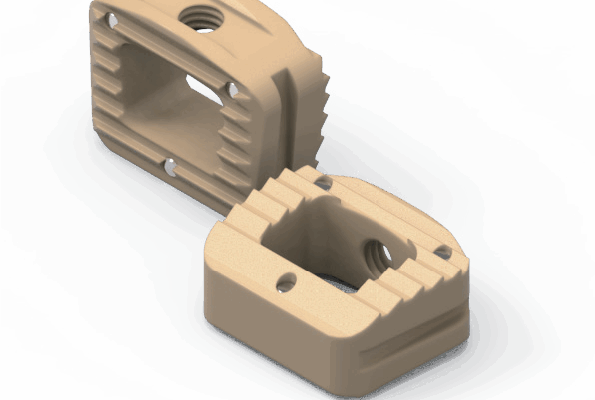

Sistema de cages para fusão intersomática, com diferentes modelos (Coales-P, C, M, T, L e Mesh), em PEEK, com marcadores de tântalo para melhor visualização e adesão óssea.

- Materiais: PEEK (ASTM F2026), Tântalo.

- Medidas: Diversas opções de altura, largura e ângulo de lordose.

- Tipo de produto: Cages intersomáticos para coluna vertebral.

- Compatibilidade: Compatível com técnicas de fusão TLIF, PLIF, ACIF, etc.

Design anatômico • Radiotransparente • Marcadores de tântalo para visualização • Reduz risco de subsistência